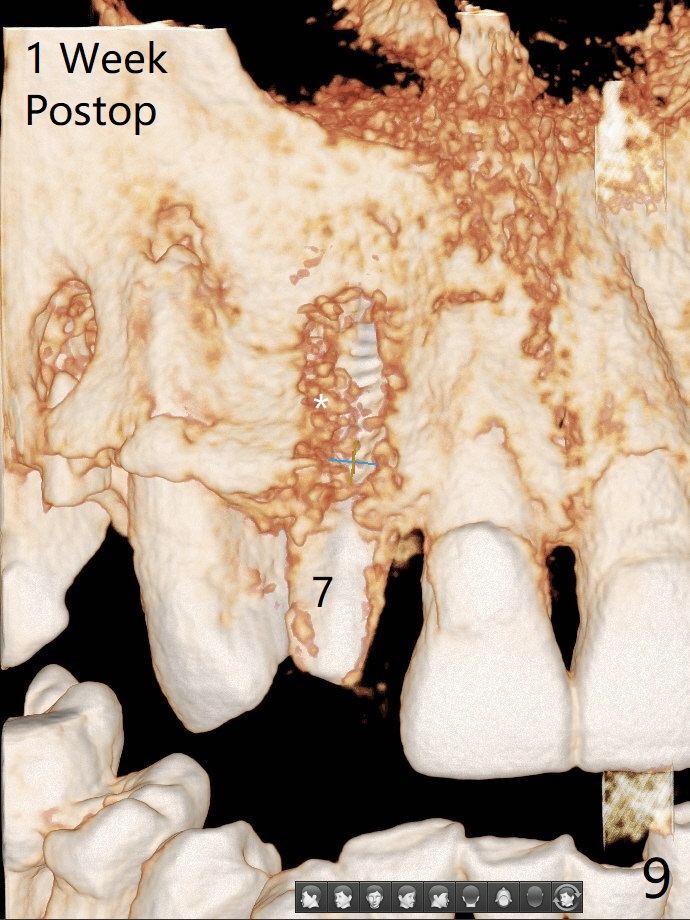

An apical abscess is present when the patient returns for immediate implant at #7 (Fig.1 *); a 2nd challenge is deep bite. After smooth extraction, the apical buccal plate is found to be perforated. Following debridement, a piece of gauze is placed in the apical defect for hemostasis, while osteotomy is initiated palatal (Fig.2). The apical defect seems to be extensive (Fig.3 yellow dashed line). A new trajectory is intended (red arrow) without much success. Before implant placement, bone graft is placed in the apical defect defect area, while a drill (Fig.4 D) is inserted in the finished osteotomy (Fig.5 O). In spite of seemingly large apical defect, the buccal crest bone exists (Fig.4 x). A 3x14(2) mm 1-piece implant is placed with stability; the first round of bone graft is apparently around the apical portion of the implant (Fig.6 *). The coronal end of the implant has to be adjusted several times buccopalatally to accommodate the deep bite. A 2nd round of bone graft following an immediate provisional closes the coronal space of the socket (Fig.7 *). CT will be taken to show the bone graft to repair the buccal plate defect when the patient returns for postop follow-up. In fact the defect is minimal in CT a month ago. The fistula does not disappear 1 week postop, but it is non tender (Fig.8). The patient complains of asymptomatic swelling in the right nostril. CT shows that the large buccal perforation is repaired with large amount of bone graft (Fig.9,10 *). It would be nicer to place the implant slightly more buccal apically (Fig.11 red lines; Fig.12 (preop design)). The buccoapical fistula disappears nearly 1 month postop (Fig.13). The apparently "lifeless" bone graft seems to be harmonious with the surrounding tissue (Fig.14). The periimplant gap reopens with implant mobility nearly 4 months postop (Fig.15), which is related to micro-movement associated with the immediate provisional. The latter is removed. A larger 2-piece implant will be placed in a 2-staged manner if needed (Fig.16). In fact the 3x14 mm straight 1-piece implant (Fig.17) has no mobility when it is retightened, but the trajectory remains buccal. Incision shows that there is no implant thread exposure. A 3x14 mm 15 degree angled 1-piece dummy implant is able to establish the correct trajectory, but there is no occlusal clearance (Fig.18). Micromovement during osteointegration may recreate loosening. Finally using Lindamann bur, the osteotomy is changed so that a 3.5x13 mm 2-piece implant does not need an angled abutment to establish occlusion (Fig.19). There is one palatal thread exposure. Allograft is placed circumferentially, followed by Human Amnion-Chorion Allograft and Collagen Plug. The wound does not heal 8 days postop (Fig.20), as related to the age (79 years old)? The wound appears to heal with a membrane on the surface (Amnion-Chorion one?) 3 weeks postop (Fig.21). The ridge looks wide 3.5 months postop (Fig.22,23). A 4.5x5.5(3) mm appears to be seated incompletely with a gap between the abutment and the implant (Fig.24<). A provisional is fabricated after heavy palatal reduction. Two months later, the provisional fractures. After repositioning the abutment with complete seating and torque (Fig.25), impression is taken. Although the buccal plate is concave, the gingiva remains healthy 10 months post cementation (Fig.26,27).